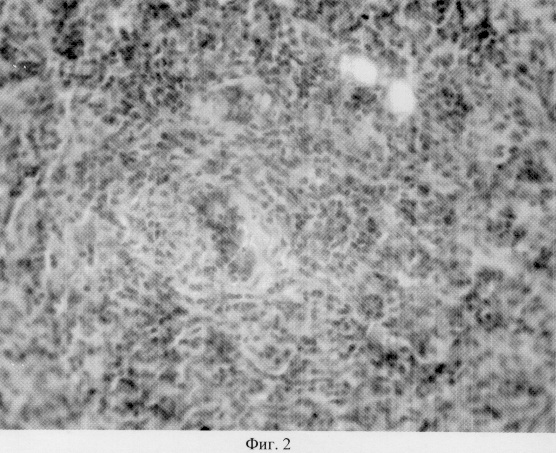

на фиг.2 показано гистологическое строение ткани щитовидной железы на 30 сутки после ее субтотальной резекции в группе без стимуляции регенерации;

Предложенный способ был апробирован в серии экспериментов на белых крысах. Были проведены гистологические исследования щитовидных желез, на 30 сутки после резекции в группе без стимуляции (фиг.2 ) и со стимуляцией (фиг.3). В первом случае наблюдается выраженная лимфо-плазмоцитарная инфильтрация, разрушающая ткань щитовидной железы. Во втором случае (фиг.3) наблюдается снижение лимфо-плазмоцитарной инфильтрации в результате подавления аутоиммунной агрессии, видны типичные фолликулы щитовидной железы, новообразованные сосуды.